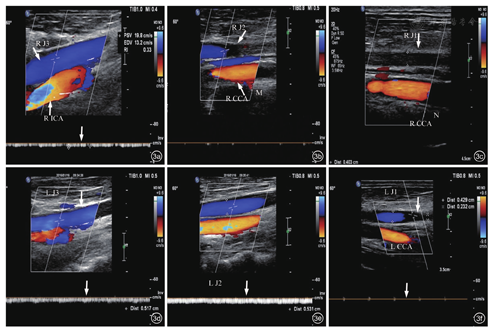

颈内静脉超声检查(2016-12-10):双侧颈内静脉(图3a, 图3b, 图3c)、双侧头臂静脉血栓形成(完全型,图3d, 图3e, 图3f)。双侧锁骨下静脉血栓(图4a, 图4b, 图4c);腹壁浅静脉逆流经大隐静脉至股总静脉下腔静脉回心,胸腹壁迂曲静脉扩张(反流,图4d, 图4e, 图4f)。

注:RICA为右侧颈内动脉;RJ3为右侧颈内静脉3段;RCCA为右侧颈总动脉;RJ2为右侧颈内静脉2段;M为中段;RJ1为右侧颈内静脉1段;N为近端;LJ3为左侧颈内静脉3段;LJ2为左侧颈内静脉2段;LJ1为左侧颈内静脉1段;LCCA为左侧颈总动脉